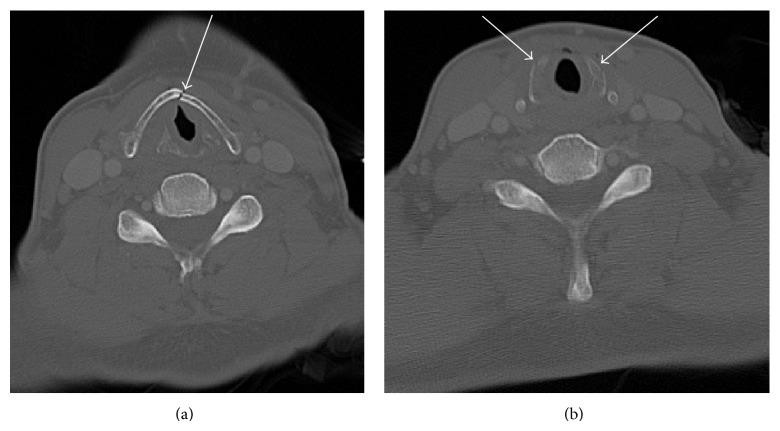

Laryngeal trauma is rare but serious and potentially deadly injury. The prompt diagnosis and management of acute laryngeal trauma is necessary because the clinical presentation is variable depending on the location, severity, and mechanism of injury. Two case histories are presented: (1) case history A: a 53-year-old male, after motor vehicle accident, fractured the mid anterior thyroid cartilage and both aspects of the cricoid cartilage; however, this patient was asymptomatic from the above fractures; and (2) case history B: a 41-year-old male who sustained trauma to the chest, neck, and left arm after being struck by a large lead pipe which fractured the left aspect of the cricoid cartilage was symptomatic. The type rather than the severity of acute laryngeal injury and the mechanism of injury may be related to symptomatology. Acute laryngeal trauma should be recognized by trauma radiologists and emergency room physicians. Early diagnosis and management of acute laryngeal trauma may prevent unnecessary specialty consults and long-term complications.